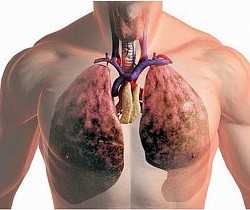

В основу статьи положен большой клинический опыт применения компьютерной томографии (КТ) у пациентов с саркоидозом органов дыхания. Саркоидоз - это системное доброкачественное заболевание, относящееся к группе гранулематозов, являющееся сегодня актуальной медико-социальной проблемой из-за высокой распространенности во всем мире. Диагностика саркоидоза - это процесс, требующий исключения ряда других заболеваний со сходной симптоматикой. И неотъемлемой частью этого процесса, наряду с клинико-лабораторными исследованиями, является рентгеновская компьютерная томография. Метод обладает высокой разрешающей способностью и позволяет отчетливо визуализировать легочную ткань и органы средостения. В статье мы продемонстрировали многообразие лучевых проявлений саркоидоза респираторной системы, обратив внимание на наиболее часто встречающиеся находки при КТ органов грудной полости: это внутригрудная лимфоаденопатия, симптом «матового стекла», единичные фокусы консолидации в легких, симптом диссеминации, интерстициальные и буллезные изменения, а также поражение листков плевры и др. Выявленные на КТ изменения позволяют определить распространенность, стадию патологического процесса, осложнения, выявить сопутствующие заболевания органов грудной клетки, прогнозировать дальнейшее течение саркоидоза и оказывать влияние на выбор лечебных мероприятий.

Саркоидоз, являясь системным заболеванием, поражает разные органы и системы, помимо респираторной системы: кожа (27%), периферические лимфатические узлы (22%), глаза (15%), селезенка (6%), центральная нервная система (4%), паращитовидные железы (4%), кости (3%). Однако известно, что 90% больных саркоидозом имеют изменения в органах грудной полости. Таким образом, клинические симптомы многообразны, зависят от ряда факторов, в том числе от этнической принадлежности пациента, формы, давности болезни, фазы, локализации и распространённости процесса, а также его активности. Среди клинических симптомов выделяют общие, т.е. неспецифические, такие как лихорадка, слабость и др., а также клинические проявления, вызванные поражением различных органов [5; 6].